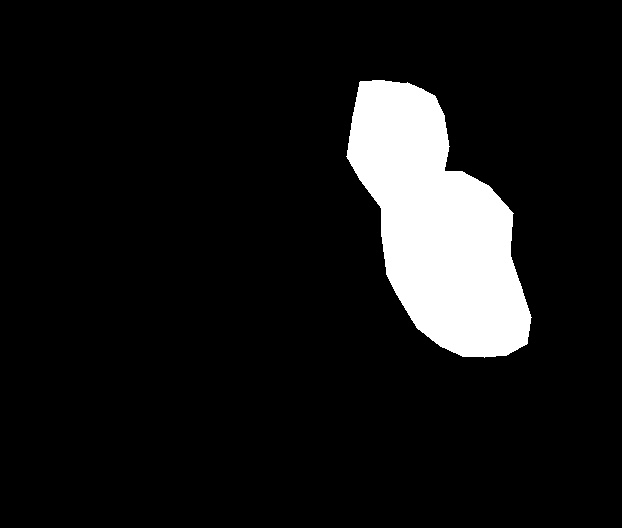

As part of the EndoCV2021 challenge (https://endocv2021.grand-challenge.org/), we were tasked with creating machine learning models that automatically segment polyps [11, 12, 13] in video frames collected from real-world endoscopies. This is a complex task as polyps come in various shapes and sizes, where some (e.g., flat lesions) are barely detectable by even the most experienced endoscopists. Figure 1 shows some of the more difficult examples taken from EndoCV’s development dataset [10] provided by the challenge organizers. The challenge presented two separate tasks, the detection generalization challenge and the segmentation generalization challenge. We participated in the segmentation generalization challenge, where we achieved the best results among 13 other competitors in both rounds. The code for the experiments presented in this paper is available on GitHub111https://github.com/vlbthambawita/divergent-nets.

Figure 4 shows some example masks predicted by our best performing model (DivergentNets) together with masks produced by the intermediate models. We see that each intermediate model learns slightly different features, making an overall more precise segmentation mask when combined. For example, the first row of Figure 4 shows the predicted masks and ground truth of a large polyp. We see that each model predicts slightly different masks for the same input and that TriUNet over-estimates the size of the polyp. After averaging the predicted masks for DivergentNets’ final output, this area is smoothed out by the predictions from the other intermediate models.